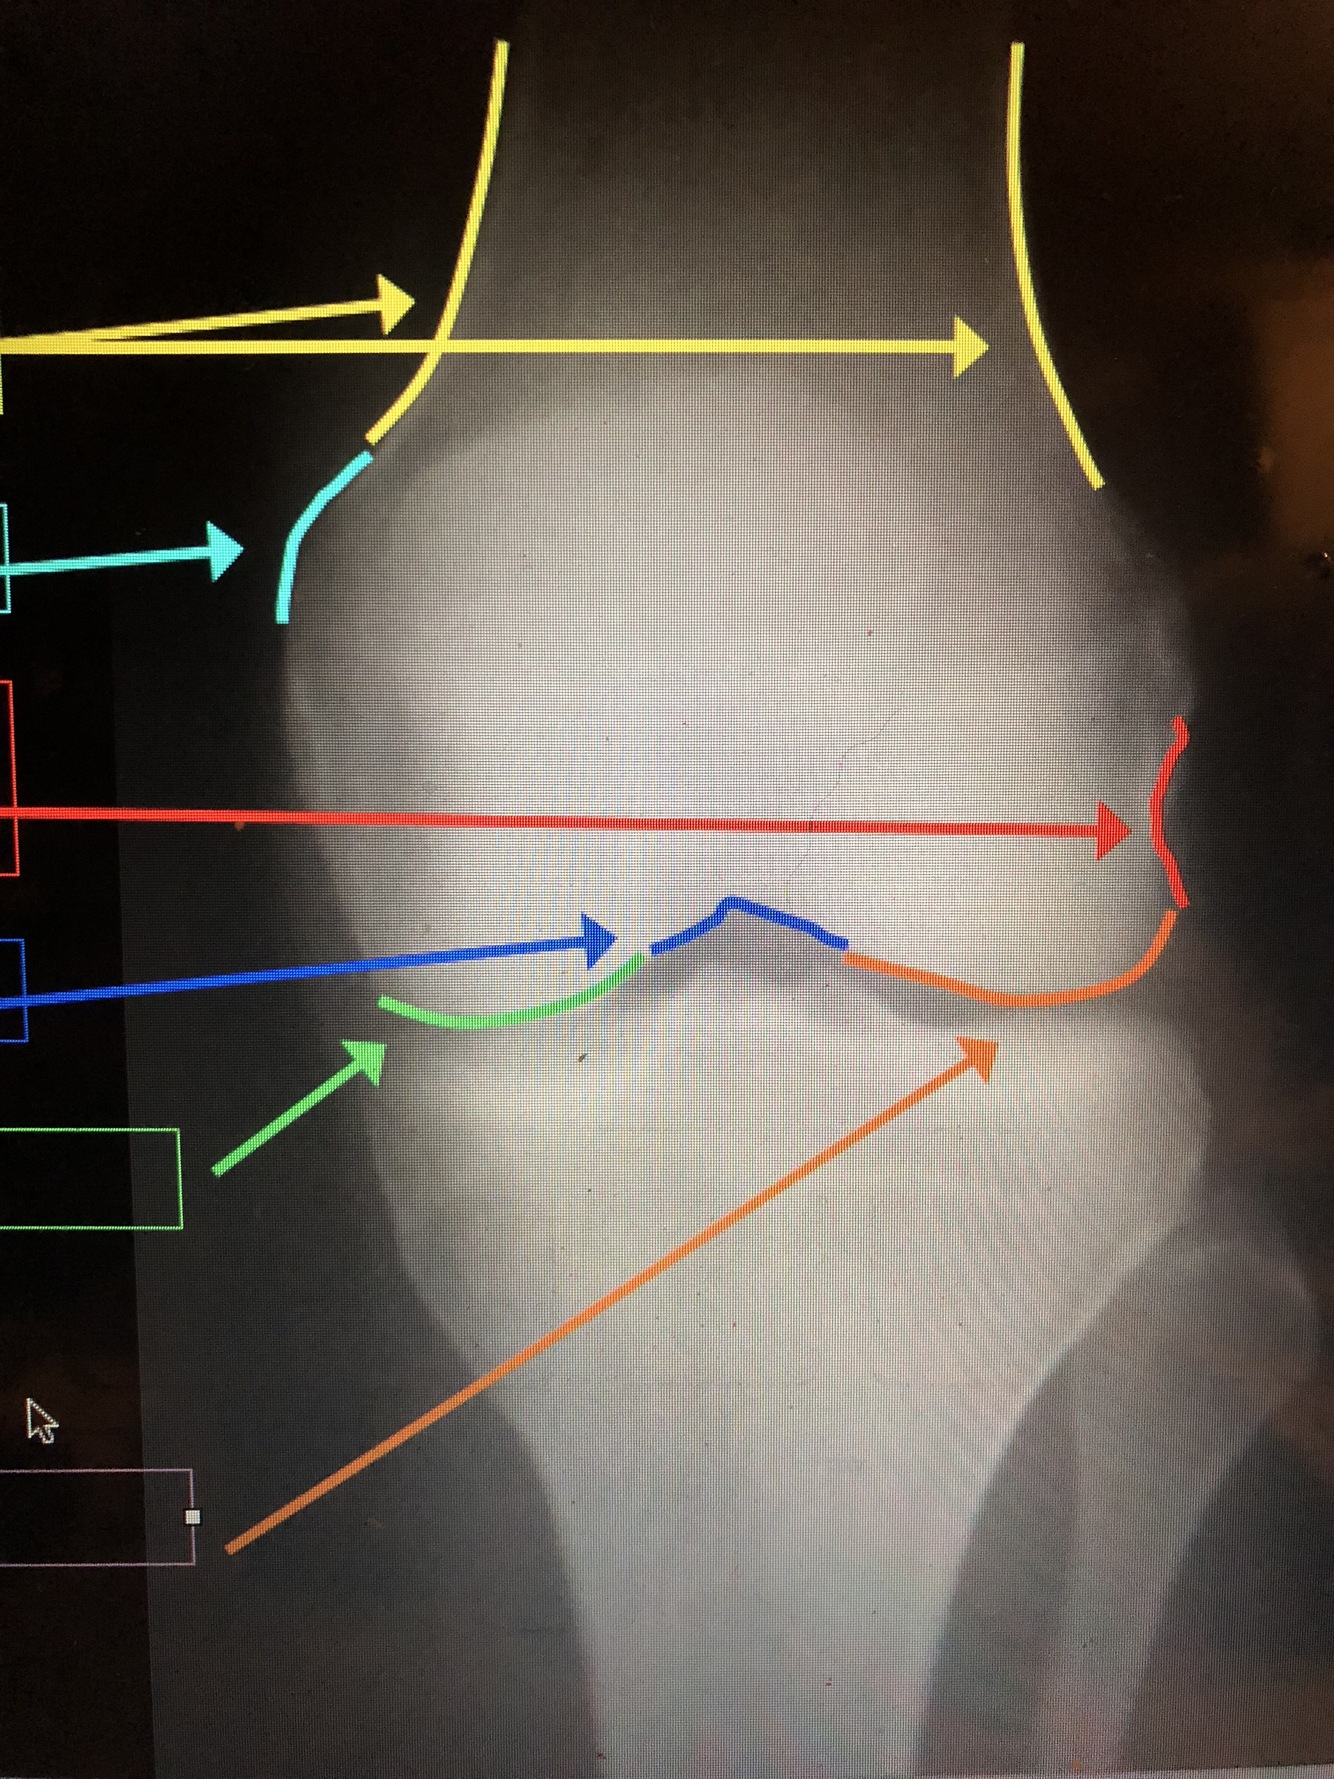

What is the light blue line?

Lateral Femoral Condyle

What is the yellow line?

Medial Femoral Condyle

Cortex – thickest at the diaphysis, but thins out near the metaphysis at the epicondyles

Q

Epicondyles (med. & lat.)

A

What is the red line?

Popliteal Groove – where popliteal tendon passes

What is the dark blue line?

Intercondylar Notch

What is the green line?

What is the orange line?